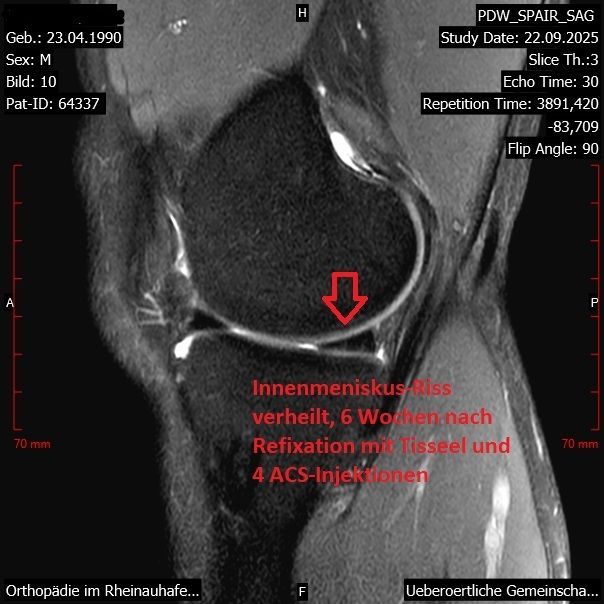

Meniskus-Riss - vor- und nach der Behandlung mit Fibrinkleber und ACS

Die Gewebe-Klebungen erfolgen ohne Operation in örtlicher Betäubung unter Kernspin-Kontrolle mit einem Fibrin-Kleber (Tisseel) und anschließend wird die Heilung durch Injektionen von Wachstumsfaktoren (ACS) gefördert. Seit August 2016 haben wir mit dieser von uns entwickelten neuen Methode über 1090 Behandlungen durchgeführt.

Nur etwa 18% davon waren nicht erfolgreich.